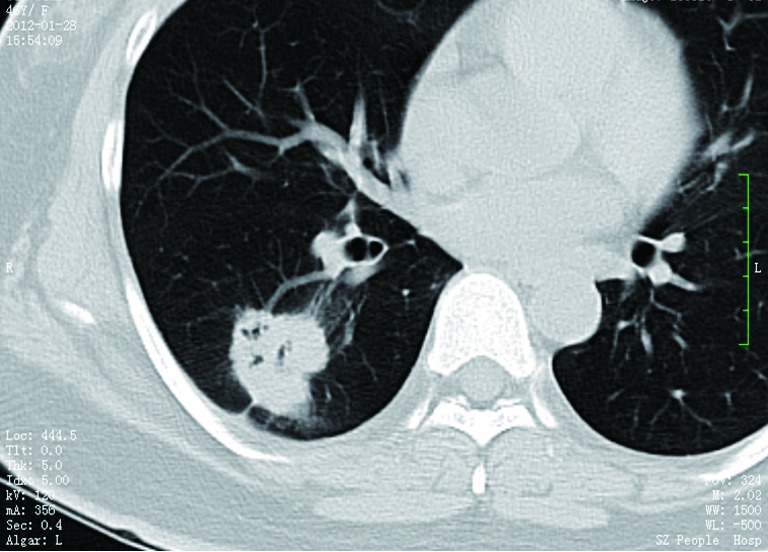

Figure 3.

CT shows a case of rounded atelectasis (arrow) with morphological features of subpleural location, curved course of blood vessels into the opacity, and evidence of pleural disease.

SPNs with irregular, spiculated margins, or lobulated contours, are typically associated with malignancy. Two patterns of the margins of a nodule are relatively specific for cancer. One is the corona radiata sign, consisting of very fine linear strands extending 4 to 5 mm outward from the nodule; they have a spiculated appearance on plain radiographs (Figures 4,5). A scalloped border is associated with an intermediate probability of cancer. Although most SPNs with smooth, well-defined margins are benign, these features are not diagnostic of benignity. A total of 21% of malignant nodules had well-defined margins (29).

Figure 4.

CT shows a pulmonary adenocarcinoma presenting as a SPN (size: 22 mm) with spiculated margins. SPN, solitary pulmonary nodule.

Figure 5.

CT shows a pulmonary adenocarcinoma presenting as a SPN (size: 30 mm) with lobular contour, spiculated margin and plural indentation. SPN, solitary pulmonary nodule.